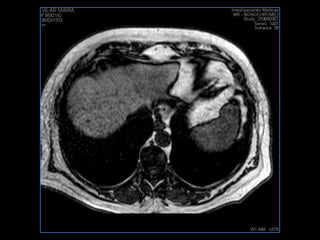

PROTOCOLO hígado graso AXIAL in phase y out phase AX T1 y AX fat sat +SAG T2  CON   GADOLINIO :  COR T1+AX T1(DIN) SAT: NO  FASE: RL THK: 4MM  COIL:  GAP: (FACTOR 1.4)  FOV: 40 CM NEX:2 SINCRONIZACION RESPIRATORIA EN 3 O 4 CICLOS ALE